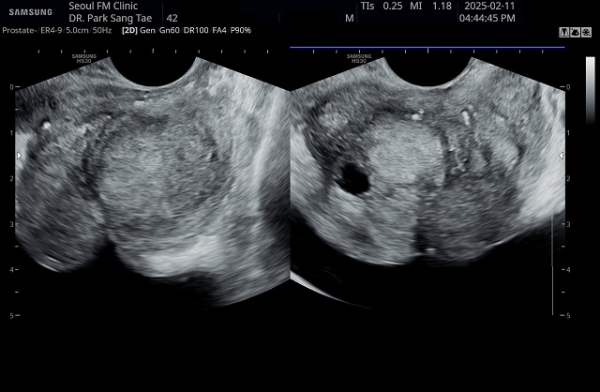

10년전부터 배뇨장애와 빈뇨로 비뇨기과에서 약을 복용중 2년전부터 급박뇨와 요실금이 심해져 투약을 했으나 증상의 호전이 없다고 내원당일 검사한 경직장 전립선 초음파 검사상 전립선 비대와 전립선의 낭종과

사정관주위의 결석이 관찰되는 경직장 전립선 초음파 사진입니다.

This is a transrectal prostate ultrasound image taken on the day of the visit. The patient had been taking medication for urinary difficulties and frequent urination for over 10 years at a urology clinic. However, since two years ago, symptoms of urgency and urinary incontinence worsened despite continued medication. The ultrasound shows prostate enlargement, cysts within the prostate, and calcifications around the ejaculatory ducts.

내원 당일 전립선의 정면 초음파 사진상 좌우 사정관 입구의 결석과 전립선의 이행구역에 비대해진 결절 그리고 우측 전립선 결절내 전립선 낭종이 관찰되며

방광쪽으로 커져 배뇨장애와 급박뇨가 심해 지고 있는 경직장 전립선 초음파 사진입니다.

This is a transrectal prostate ultrasound image taken on the day of the patient's first visit, showing stones at the openings of both ejaculatory ducts, an enlarged nodule in the transitional zone of the prostate, and a prostatic cyst within the right prostatic nodule. The prostate is enlarged toward the bladder, contributing to worsening voiding dysfunction and urgency.